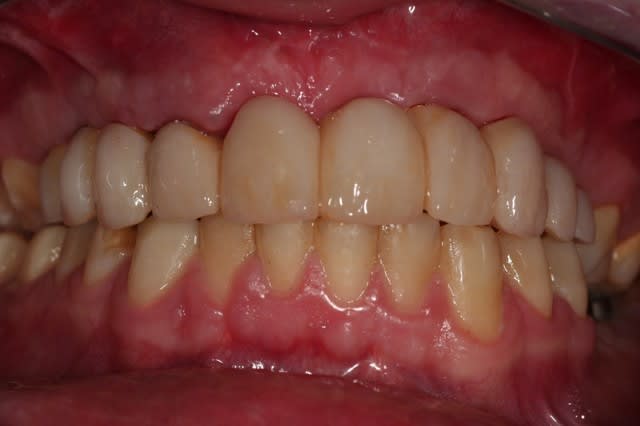

voilà, ça prend forme.

deuxième bridge provisoire.

j'ai sous-estimé le décalage de la 22, on y réfléchit.

je laisse mûrir complètement comme ça, et on verra à la fin si on fait de la mucco gingivale.

le patient est très content et s'en fout.

semaine prochaine: endos, compos et inlays....

Provisoire2  tloahq - Eugenol